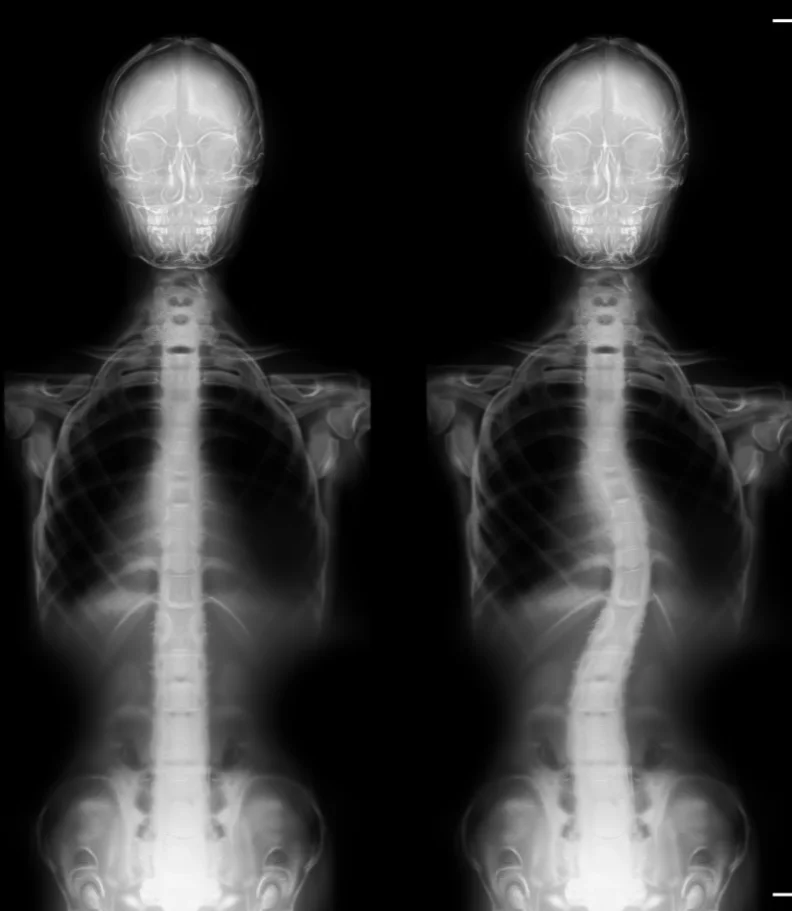

Scoliosis is characterized by an abnormal curve in the spine, deviating from its normal vertical alignment. The exact cause of this curvature can be difficult to pinpoint. In its early stages, it may start as a minor bend due to a single vertebra's misalignment. Over time, the body compensates by developing muscles that pull the spine into further curves to maintain a level head position.

Often, parents or close associates first notice scoliosis when the shoulders and pelvis appear uneven. A thorough physical examination assesses gait and uses visual and manual evaluations to determine the extent of spinal curvature. An Adams Position Test, where the patient bends forward as far as possible, can reveal any issues. If a significant curvature is detected, an X-ray is used to assess the severity of scoliosis.